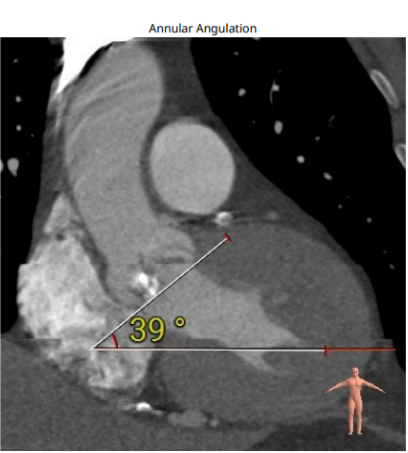

三叶瓣,瓣环偏大,右无瓣叶钙化重;LVOT直径小于瓣环直径,呈漏斗形;窦部直径可,STJ及升主直径偏小,双冠脉高度可;主动脉根部角度约39°;室间隔及室壁增厚,LV偏小。